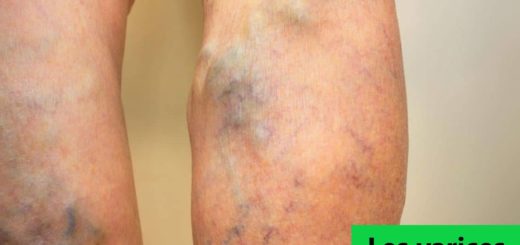

Une sensation de jambes lourdes ? des démangeaisons ? certaines douleurs qui vous penser à des crampes ? C’est ainsi que débute les varices. C’est d’ailleurs quelques uns de ses symptômes que vous ressentirez....